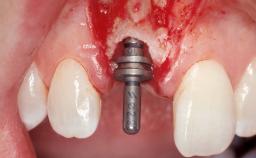

Late Placement of an Implant in a Maxillary Left Central Incisor Site

A 36-year-old female patient was referred for the replacement of the upper left central incisor (tooth 21), which had fractured. Although the tooth had been asymptomatic for many years, the crown began to loosen, at which time she presented to her dentist for an assessment. Teeth 21 and 22 had both been endodontically treated many years previously. She was a healthy individual and a non-smoker.

Bone Augmentation | Horizontal|Staged |

Augmentation Materials | Xenogenous|Membrane |

Soft Tissue Grafting | Simultaneous |